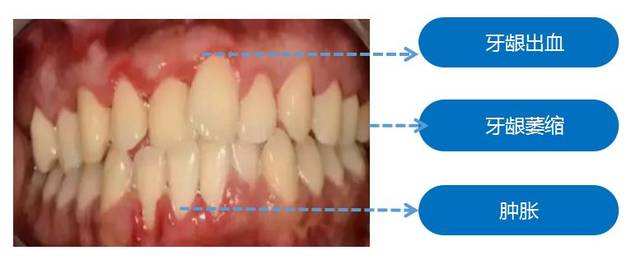

牙龈是在牙齿周围以及牙槽骨上富有韧性的淡红色结构。它有丰富的血管,并且无法移动。

有时我们照镜子会发现,自己的牙齿变的细长,肉眼可以见到包裹牙齿的"红肉"向下消退,这就是牙龈萎缩现象。

这种症状主要来自于我们的牙周疾病,和不良的生活习惯:

第一,不合理的选择牙刷和使用牙刷,长时间就会影响牙龈使其发生萎缩。例如,用很大的力气刷牙,刷牙方向和方法不正确。

第二,不合理的使用剔牙产品,会导致牙龈萎缩的情况出现。

第三,如果在治疗口腔问题时做了不合适的操作,或者佩戴质量不是很好的假牙,都有可能导致牙龈萎缩问题。

第四,日常生活中对口腔清洁如果疏于管理,引起牙周疾病,就会导致牙龈萎缩。